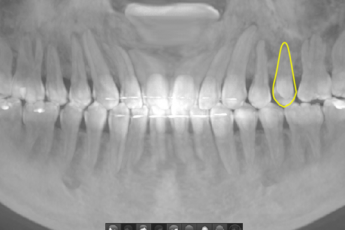

- 매복치교정